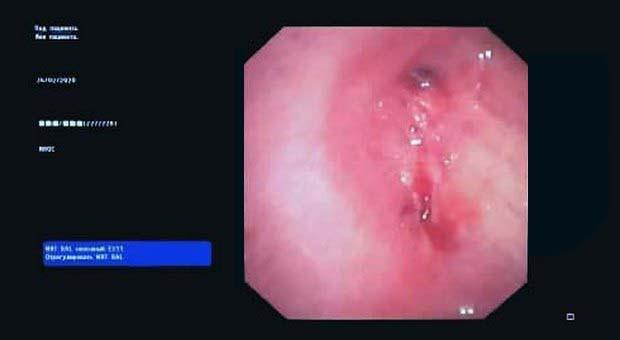

Вчера в отделении эндоскопии успешно апробировано окклюзия бронхоплеврального свища.

Пациент К. 1960 г.р., после правосторонней пульмонэктомии от 2019 г. поступил в отделение многоплановой хирургии. При плановой бронхоскопии выявлена несостоятельность культи правого главного бронха, устье свища до 0.3 см, откуда поступает слизисто-гнойное содержимое. В устье свища определяется сшивающая скоба. Также у пациента имеется дренажная трубка справа в 7 межреберье, подключаемая к активному отсосу.

Во время повторной бронхоскопии под интубационным наркозом установлен окклюдер из ИМН другого назначения (PULL THRU) в устье свища. Поперечные резиновые лепестки на окклюдере и скоба в устье свища должны надёжно фиксировать положение окклюдера.

Оборудование: видеобронхоскоп Olympus 180, окклюдер PULL THRU( Medivators)